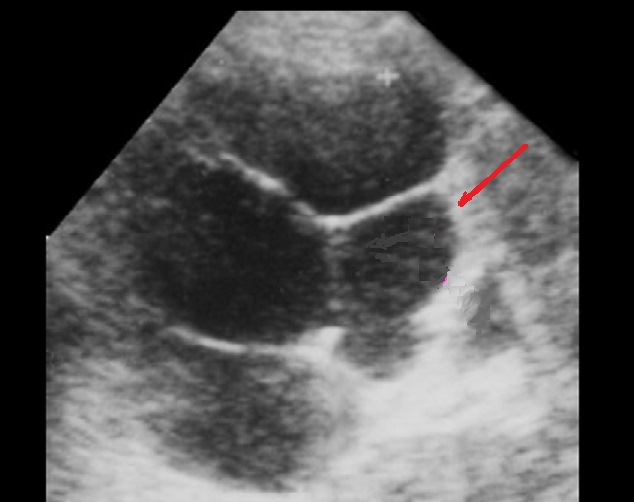

Aspect radiologique du cystadenome

sereux multikystique de la tete du pancreas . La

tumeur est comporte par des kyste a moindre 2cm a

hypodense , de contour et cloison septal interne

sont nette , Image radiologique TDM non contrast

intraveineuese , coupe axiale . |